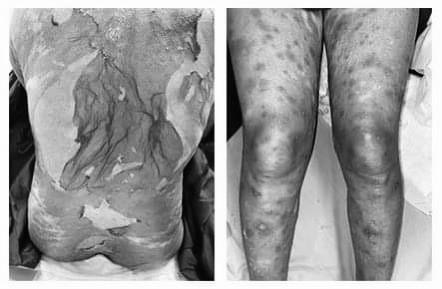

Trường hợp bệnh thứ hai là bệnh nhân nữ, 55 tuổi, nhập viện Khoa Bệnh da phụ nữ và trẻ em, Bệnh viện Da liễu Trung ương vì các dát thâm hoại tử và vết trợt da. Bệnh diễn biến bảy ngày trước khi vào viện.

Ban đầu, bệnh nhân xuất hiện dát đỏ thẫm, sưng nề vùng môi, sau đó các dát đỏ lan nhanh ra tay, chân, thân mình, hình thành thêm mụn nước, bọng nước. Có sốt cao. Khám lúc vào viện thấy dát đỏ thẫm, liên kết với nhau thành mảng, bọng nước, hoại tử da lan tỏa. Các niêm mạc không có thương tổn. Các xét nghiệm của bệnh nhân có hạ bạch cầu và tăng men gan.

Bệnh nhân được chẩn đoán hoại tử thượng bì nhiễm độc (hội chứng Lyell) và điều trị tích cực tại khoa, dùng các thuốc đặc hiệu (corticoid toàn thân) kèm chăm sóc hỗ trợ. Sau 7 ngày điều trị, thương tổn da khô, bắt đầu tái tạo thượng bì, không có bọng nước mới.